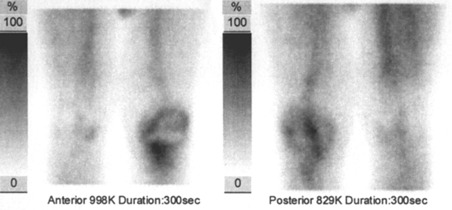

Medical). V první i druhé fázi scintigrafie byla zvýšená depozice radiofarmaka v oblasti celého pravého kolenního kloubu kolem femorální i tibiální komponenty TEP. Ve druhé fázi je zvýšena depozice radioindikátoru v oblasti mediálního kondylu pravé

tibie. Tento nález svědčí pro zvýšenou perfuzi (prokrvení) v oblasti levého kolena a v oblasti mediálního kondylu pravé tibie

(obr.1, 2).

/ Obr. č. 2: Třífázová scintigrafie skeletu – 2. fáze tkáňová (tzv. blood pool), scintigrafie kolenních kloubů v přední a zadní projekci /